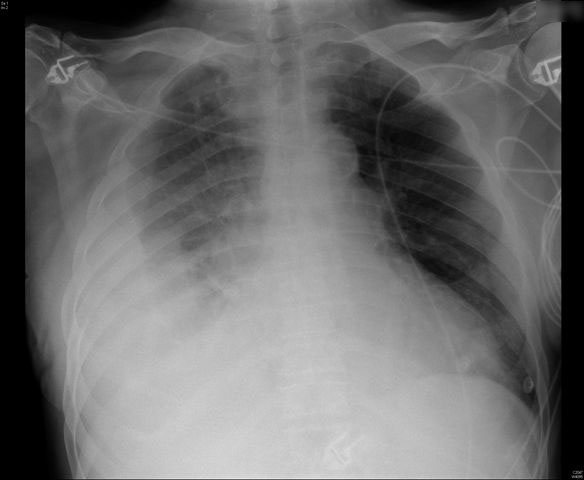

APR Derrame pleural derecho